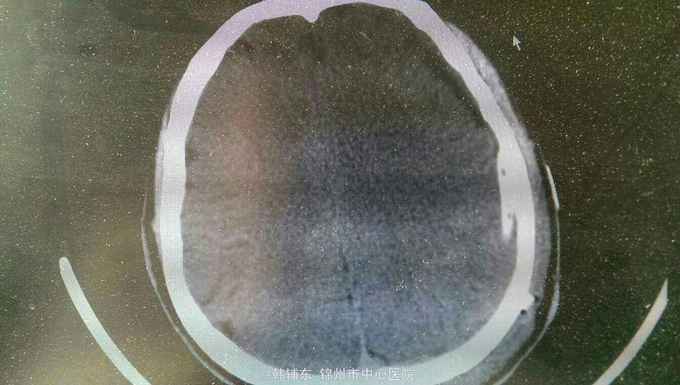

神志清楚,语言流利。神经系统无阳性体征,双侧瞳孔等大正圆直径3.0毫米,光反射灵敏。四肢肌力正常,生理反射存在,病理反射未引出。头部核磁共振显示如下。

诊断:亚急性硬膜下血肿。行血肿钻孔引流术。术后引出陈旧血,患者头痛缓解。

亚急性性硬膜下血肿绝大多数有轻微头外伤史,尤以老年人额前或枕部着力。亚急性颅内压增高症状常于伤后1~3个月后出现如头痛、视物模糊、一侧肢体无力等。精神智力症状表现为记忆力减退、智力迟钝、精神失常等。局灶性症状表现为轻偏瘫、失语等。亚急性或慢性硬膜下血肿MRI的T1和T2均表现为高信号。首选颅骨钻孔冲洗闭式引流术。对于血肿囊壁肥厚伴钙化须行骨瓣开颅清除血肿术。